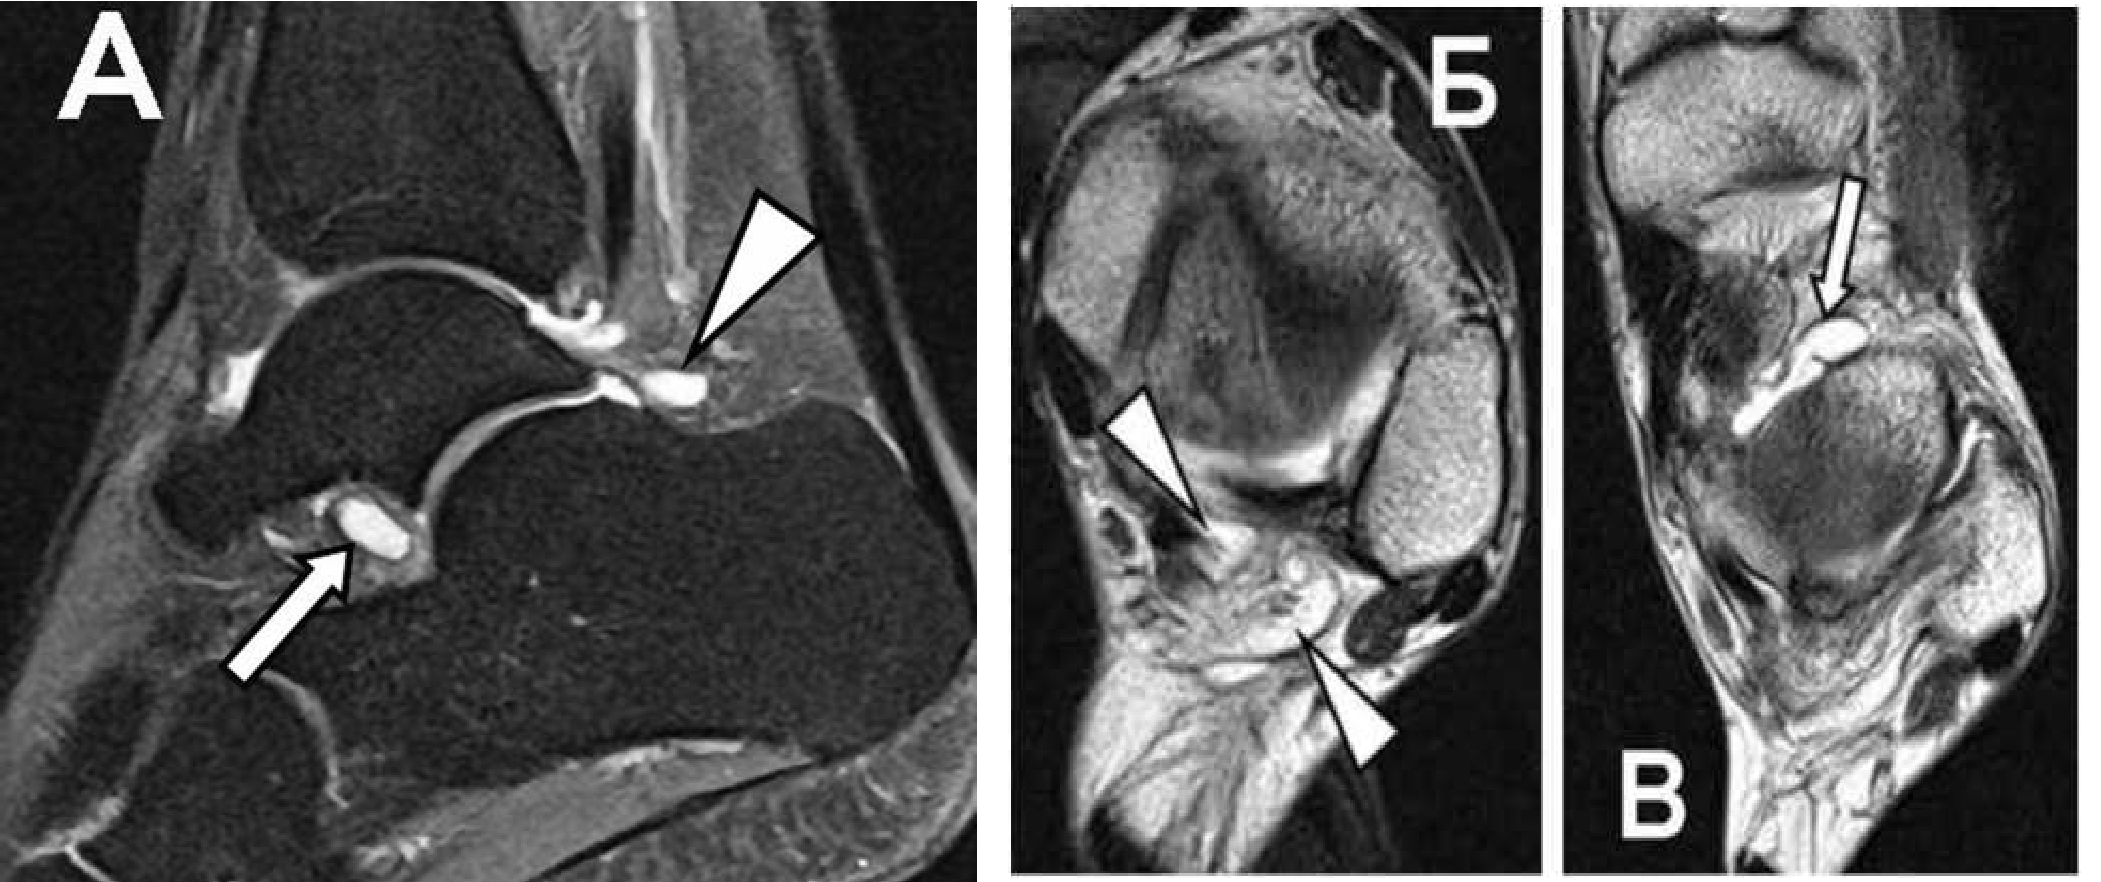

Рис. 5. Сочетание заднего импинджмент-синдома и синдрома таранного синуса у профессионального спортсмена с жалобами на боль в голеностопном суставе без анамнеза острой травмы.

А: Сагиттальная FS PD FSE томограмма показывает синовиальные кистозные разрастания по задней поверхности голеностопного сустава (треугольная стрелка) и в проекции таранною синуса (обычная стрелка).

Б: синовиальные кисты в нижней части межберцового синдесмоза (треугольные стрелки) на PD FSE томограмме в аксиальной проекции.

В: синовиальные кисты в проекции таранного синуса (обычная стрелка) на PD FSE томограмме в аксиальной проекции. Тот же пациент.